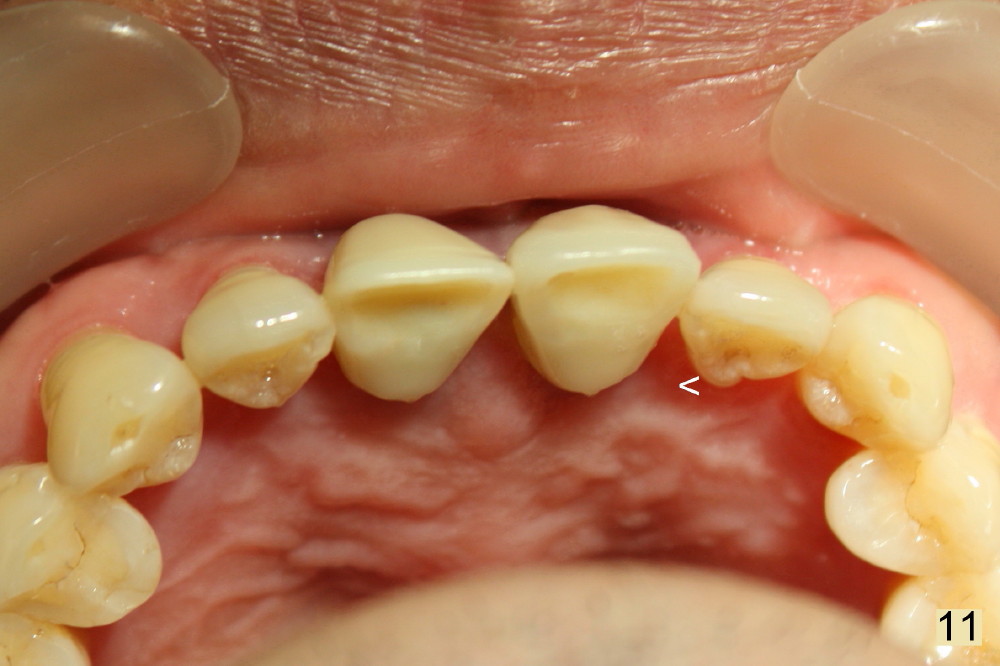

One week postop, the periodontal infection is completely resolved (Fig.10,11). There is no abnormality associated with the nasal cavity.